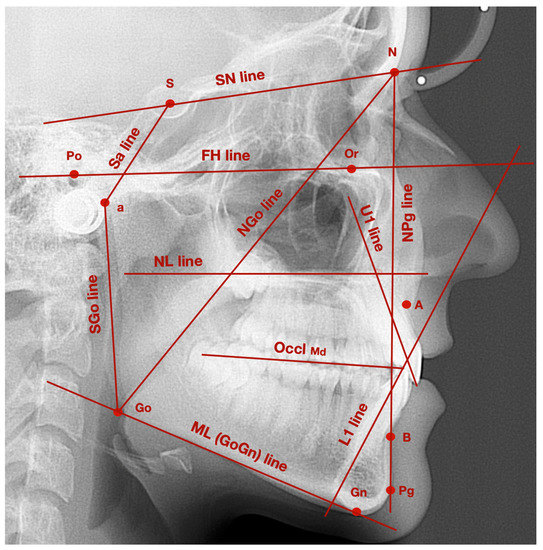

| Points/Lines/Angles | Description of Points/Lines/Angles |

|---|---|

| Point S | Sella—geometrical center of Sella turcica |

| Point N | Nasion—the most anterior point localized in the frontonasal suture |

| Point Go | Gonion—point localized at the intersection of mandibular line and line tangent to the posterior border of mandibular ramus |

| Point a | Articulare—point localized at the intersection of sphenoid bone base and the posterior part of condylar outline |

| Point Po | Porion—the most superior part of external acoustic opening |

| Point Or | Orbitale—the most inferior point localized in the lower margin of the orbit |

| Point A | Subspinale—the deepest point localized in the anterior outline of the maxilla, below the anterior nasal spine |

| Point B | Supramentale—the deepest point localized in the anterior outline of the mandible, above the pogonion |

| Wits | AO-BO—the distance between the perpendicular projection of points A and B onto the functional occlusal plane |

| Point Pg | Pogonion—the most prominent point localized in the osseous outline of mental tuberosity |

| NL line | Nasal line—line between anterior and posterior nasal spines |

| ML line | Mandibular line—line between gnathion and the lowest point localized in the masseteric tuberosity (also known as GoGn line) |

| FH line | Frankfort horizontal line—line between points: porion and orbitale |

| L1 line | Long axis of lower incisor—line which connects the incisal edge with the radiological apex of lower incisor |

| U1 line | Long axis of upper incisor—line which connects the incisal edge with the radiological apex of upper incisor |

| OcclMd | Mandibular occlusal plane—line which connects the anterior cusp tips of lower first molars with the incisal edges of the lower central incisors |

| SN line | Sella-nasion line—line of anterior cranial base, which connects points: nasion and sella |

| Sa line | Line which connects points: sella and articulare |

| aGo line | Line which connects points: articulare and gonion |

| NGo line | Line which connects points: nasion and gonion |

| NPg line | Line which connects points: nasion and pogonion |

| SNPg angle | Angle between SN line and NPg line |

| NL/ML angle | Angle between NL line and ML line |

| FMA angle | Angle between FH line and ML line |

| FMIA angle | Angle between FH line and long axis of lower incisor |

| IMPA angle | Angle between long axis of lower incisor and ML line |

| L1/U1 angle | Interincisal angle—angle between long axes of lower and upper incisors |

| L1/OcclMd angle | Angle between long axis of lower incisor and mandibular occlusal plane |

| NSa angle | Saddle angle—angle between SN line and Sa line |

| SaGo angle | Articular angle—angle between Sa line and aGo line |

| aGoGn angle | Gonial angle—angle between aGo line and GoGn line |

| aGoN angle | Upper gonial angle—angle between aGo line and NGo line |

| NGoGn angle | Lower gonial angle—angle between NGo line and GoGn line |